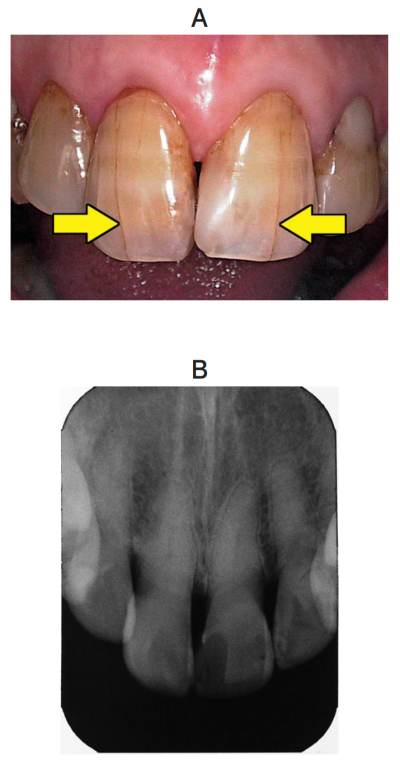

67歳の女性。両側の上顎中切歯の亀裂の精査を希望して来院した。友人に指摘されて心配になったという。本人は見た目を気にしていない。自発痛や誘発痛はなく、歯髄電気診で正常反応を示した。矢印で亀裂を示した初診時の口腔内写真とエックス線写真を別に示す。

適切な対応はどれか。1つ選べ。

a. 経過観察

b. フッ化ジアンミン銀塗布

c. バイタルブリーチ

d. ラミネートべニア修復

e. 抜髄